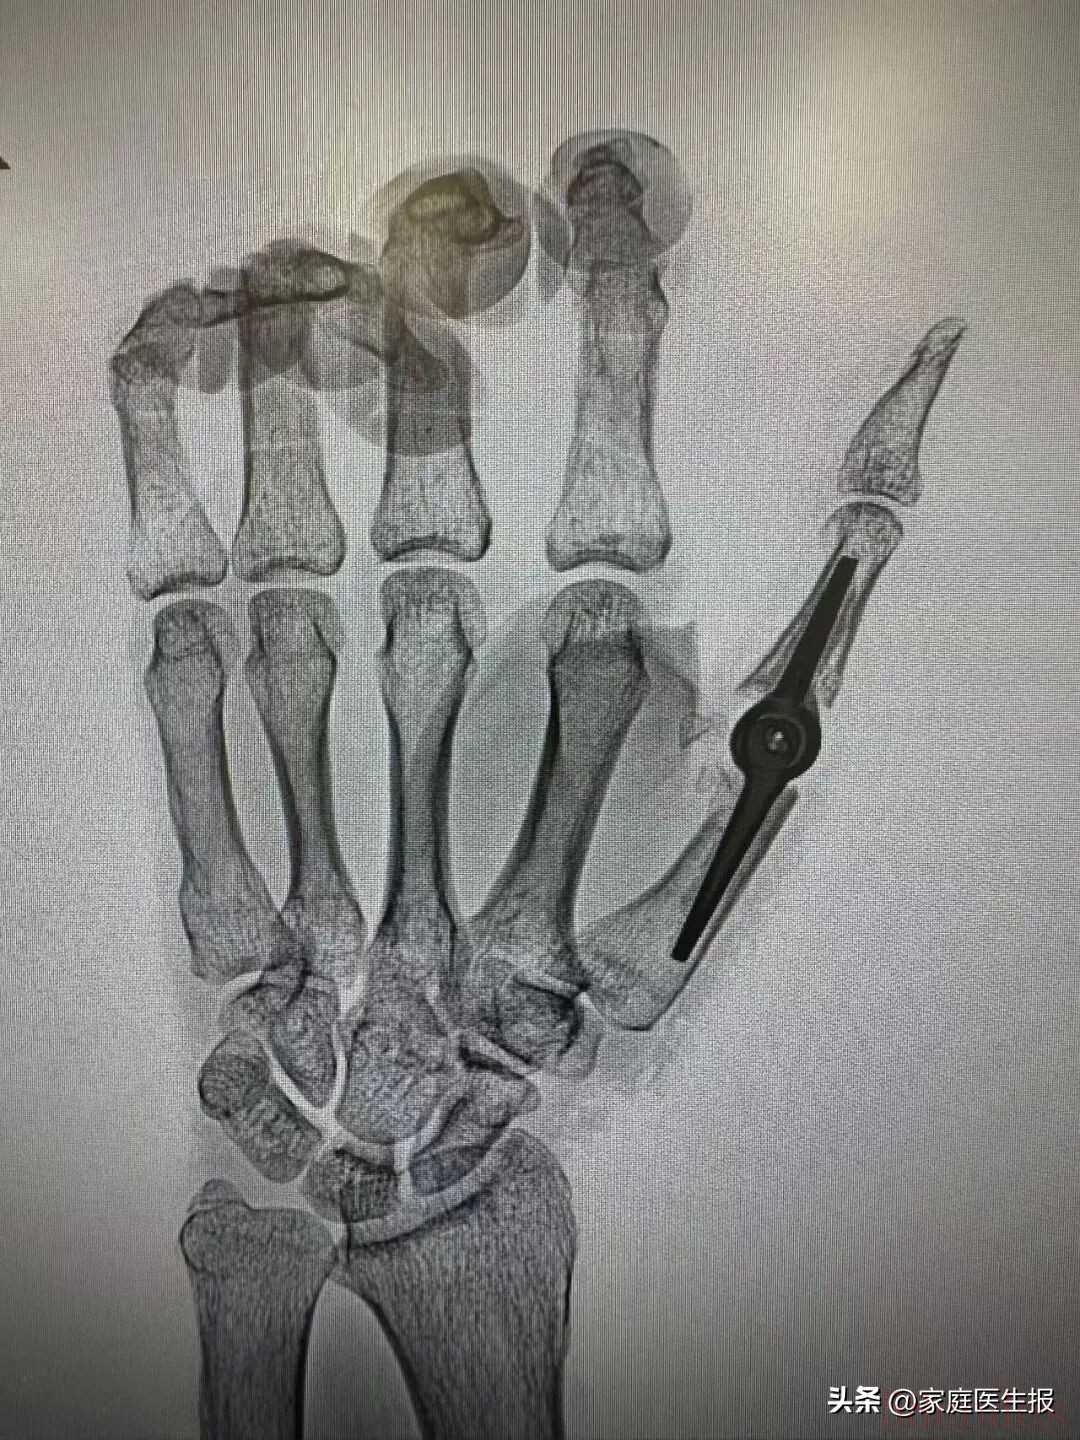

手术中当医生看到李先生拇指掌指关节处严重的肌腱粘连与关节僵硬时更坚定了置换的决心一枚通过3D打印技术精密制造的铰链式金属假体被精准植入替换掉已失去功能的关节面再用骨水泥牢牢固定——一个冰冷的“铁疙瘩”就这样在他手中有了“生命的温度”

手术中当医生看到李先生拇指掌指关节处严重的肌腱粘连与关节僵硬时更坚定了置换的决心一枚通过3D打印技术精密制造的铰链式金属假体被精准植入替换掉已失去功能的关节面再用骨水泥牢牢固定——一个冰冷的“铁疙瘩”就这样在他手中有了“生命的温度”术后康复的节奏紧凑而温暖术后第一天康复治疗师便介入指导开始早期、系统的关节被动活动防止粘连“卷土重来”